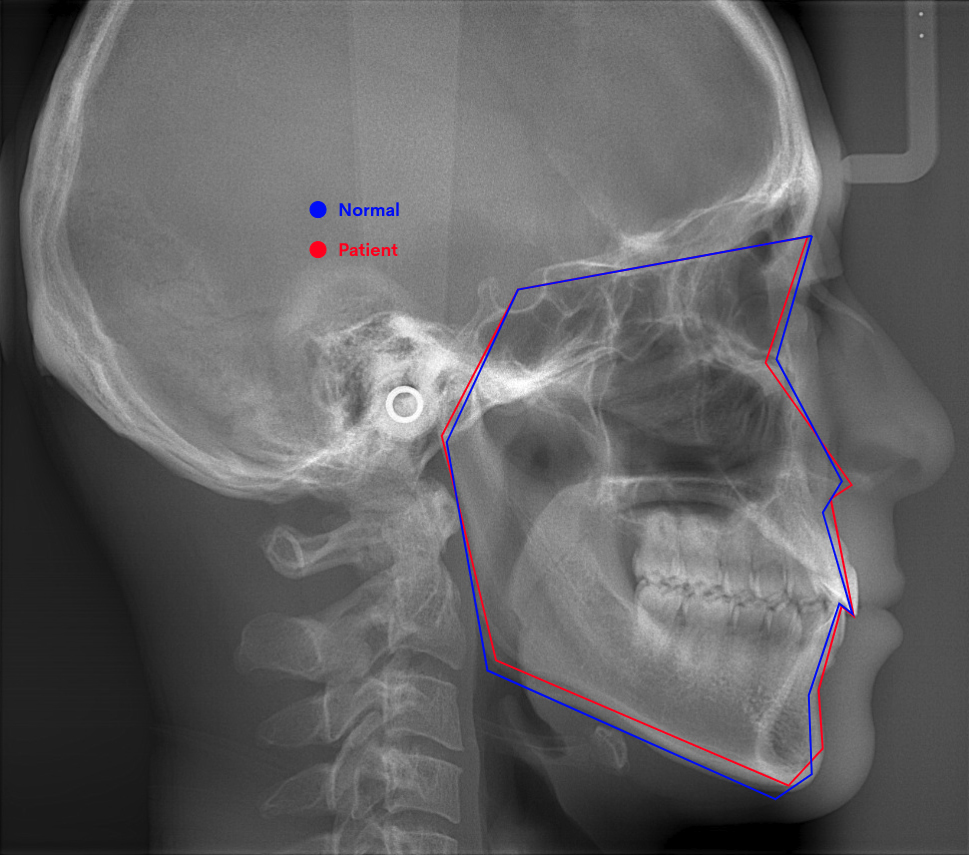

精密検査では、お口の中の写真・レントゲン・CT・顔貌を診るためのお顔の写真を撮影します。

さらに、歯型の採取、口腔内スキャナ(iTero)による詳細なスキャニングも実施。

歯だけでなく、顎関節や顎の骨、頭部全体のデータを採取し、治療計画を立てていきます。

頭部全体のレントゲン写真